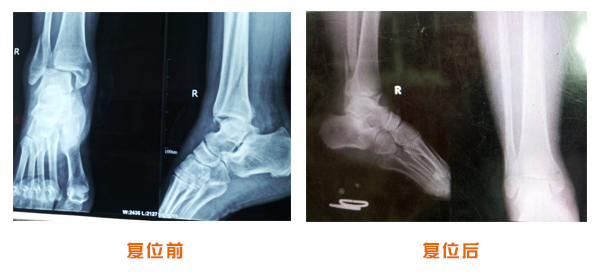

復位前后對比